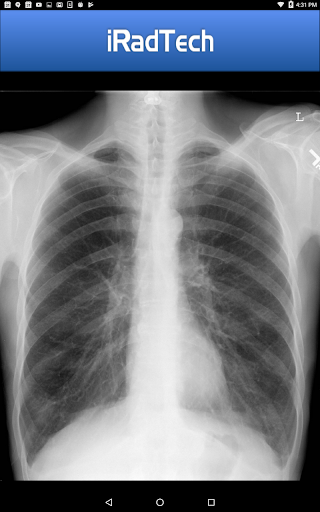

The app provides technical factors, image receptor specifications, patient positioning guidance, respiration instructions, and precise central ray details. It also features representative radiographic images that can be enlarged for better inspection, ensuring accurate positioning and image quality.

One standout feature is the enlargeable photographs of properly positioned human models, clearly showing the collimated area with central ray entry points. Additionally, each position contains a helpful NOTE tab where users can save techniques or other relevant information.

iRadTech's representative radiographic images and properly positioned human model photographs further support teleconsultation quality. These enlargeable visuals help practitioners verify correct positioning and collimation, leading to better communication and understanding between healthcare providers and patients.